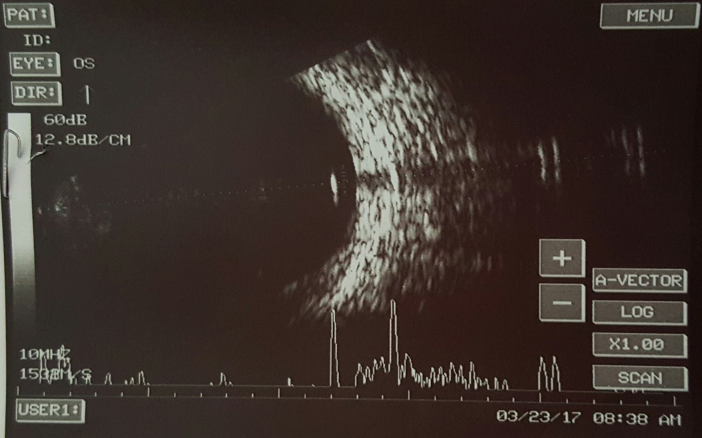

A 10-year-old boy presented to the emergency with a history of blast injury. His visual acuity at presentation was 6/6 in the right eye and hand movements in the left. Ocular examination showed a full thickness corneal laceration measuring 10 mm passing through the center of the left cornea. He underwent corneal tear suturing with lens extraction as an emergency procedure by the cornea team (Figure 1 [Fig. 1]). Intraoperatively, there was a posterior capsular rent with cortex drop which necessitated a pars plana vitrectomy. During pars plana vitrectomy, three non-metallic foreign bodies ranging in size from 0.5 to 2 mm were removed from the posterior segment. Perfluoro-n-octane was used to assist the surgical removal. The visibility throughout the surgery was poor due to the corneal wound. On the first postoperative day, the posterior segment could not be examined clinically due to corneal edema and astigmatism. Ultrasonography of the posterior segment revealed a high reflective echo with back shadowing in the posterior vitreous (Figure 2 [Fig. 2]). A plain computed tomography scan (CT) was done which revealed a round, 1.9 mm x 2.1 mm sized radio dense (400 Hounsfield units) lesion close to the retina in the left globe (Figure 3A [Fig. 3]). With the suspicion of a retained intraocular foreign body, the patient was taken up for a repeated pars plana vitrectomy. Intraoperatively, there was no evidence of a foreign body. Instead, there was a small bubble of perfluoro-n-octane over the posterior pole. The bubble was aspirated. CT scan was repeated in the postoperative period which showed the absence of any radio dense lesion (Figure 3B [Fig. 3]).

Figure 2: Ultrasonography following the initial surgery showing a hyperintense lesion with backshadowing suggestive of a foreign body